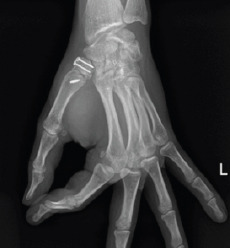

Radiographically, no fracture loss of fixation, reduction, or articular instability was observed during follow-up. Fracture healing and joint congruence without signs of osteoarthritis were observed after 1 year of follow-up (Fig. 5.1, 5.2).

Figure 5.1.

One-year follow-up X-ray: Anteroposterior view.

Figure 5.2.

One-year de follow-up X-ray: Oblique view.